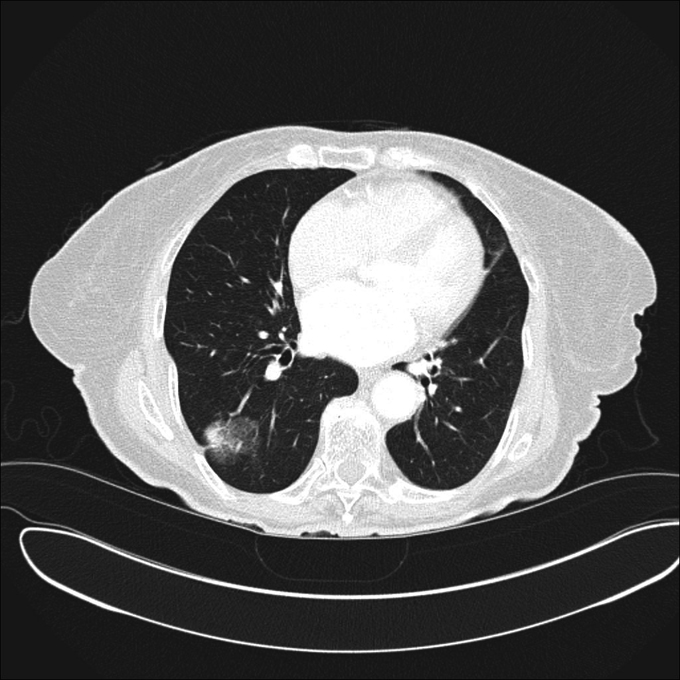

| Nodul pulmonar solid. Sursa foto: Medscape.com - Solitary Pulmonary Nodule |

| Nodul pulmonar solid care s-a dovedit a fi metastaza de la un cancer de colon. Sursa foto: Medscape.com - Solitary Pulmonary Nodule |